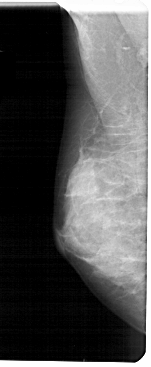

A_1606_1.RIGHT_MLO

LEFT_MLO LINES 5491 PIXELS_PER_LINE 2251 BITS_PER_PIXEL 12 RESOLUTION 43.5 NON_OVERLAY